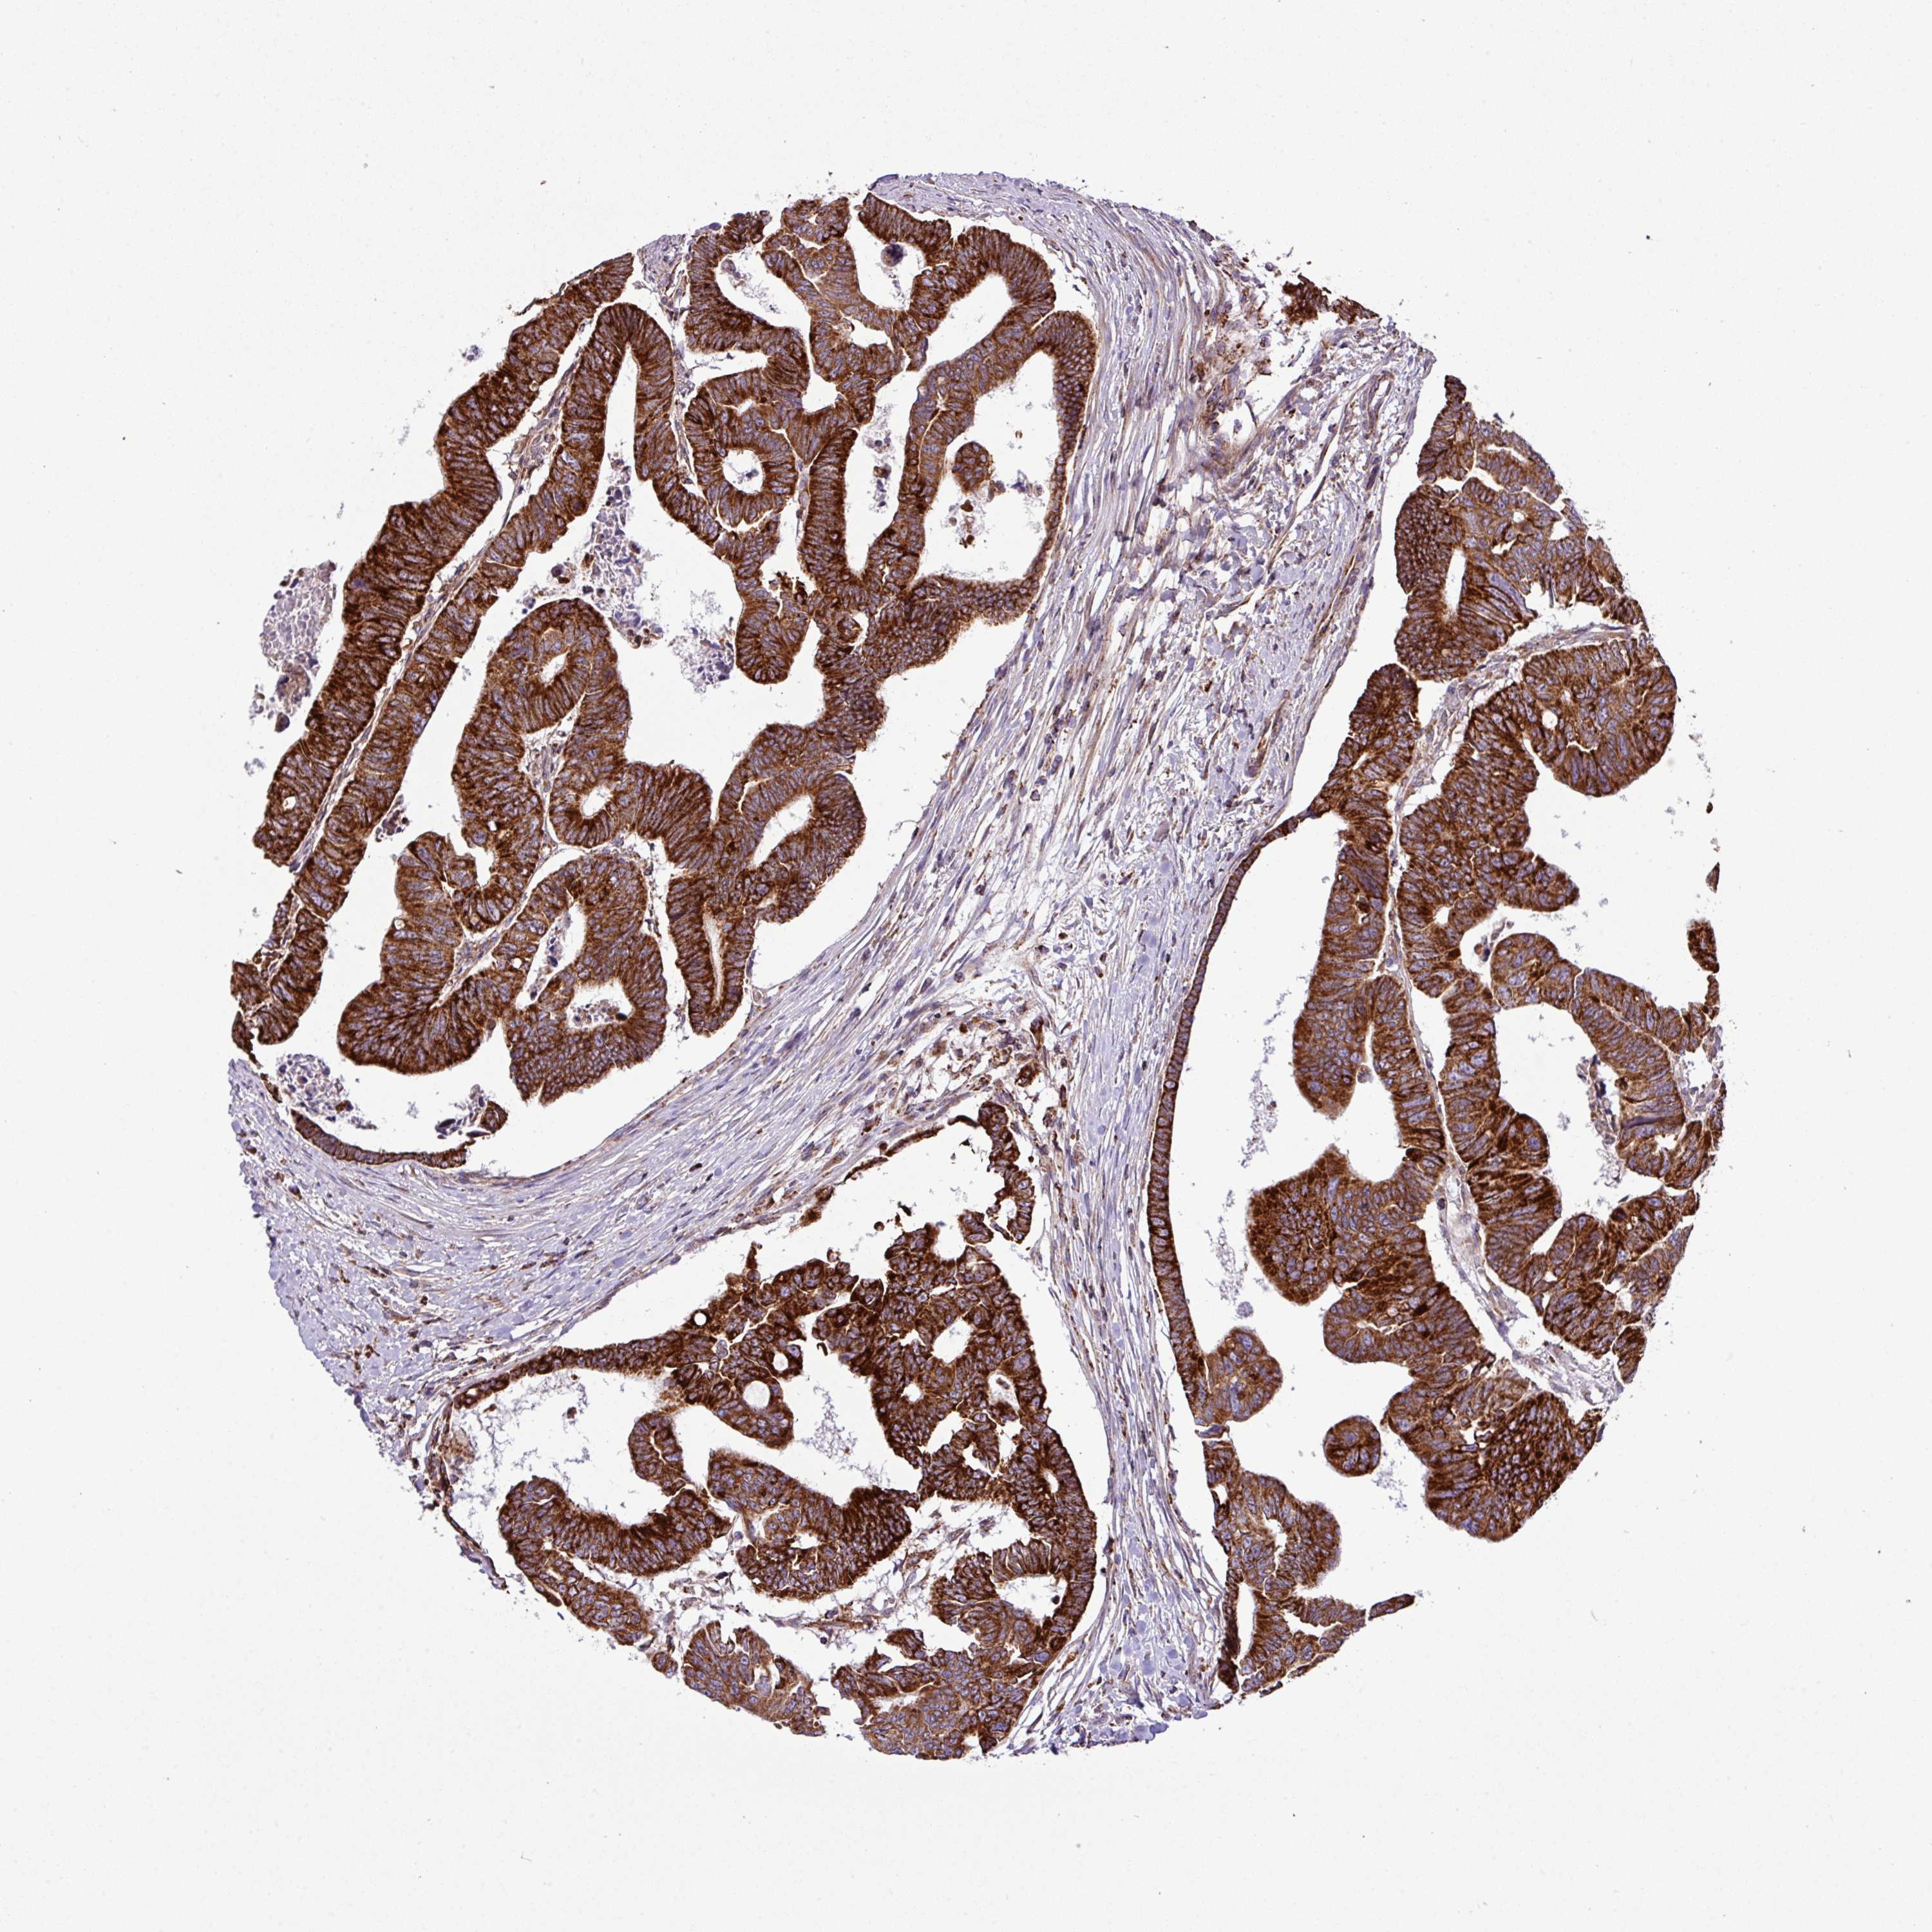

CANCER COLORECTAL CANCER Show tissue menu

Colorectal cancer

Human cancer

Colon adenocarcinoma

Rectum adenocarcinoma